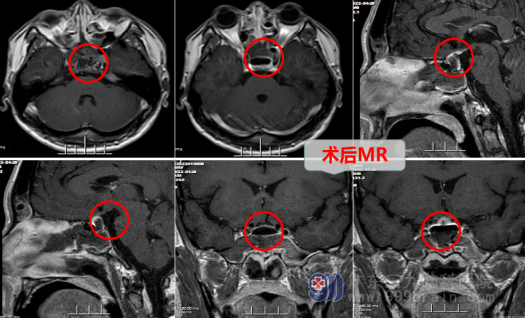

在得到家属和病人的同意之后,医生在4月28日对闫大哥实施了“内镜经鼻蝶鞍区Rathke`s囊肿切除术”。手术很成功,术后复查头部MR检查:原病灶(囊肿)已切除,已消失。病理诊断结果也的确是Rathke`s囊肿,经过术后一周的恢复,内分泌检验结果也恢复正常,闫大哥顺利康复出院了。